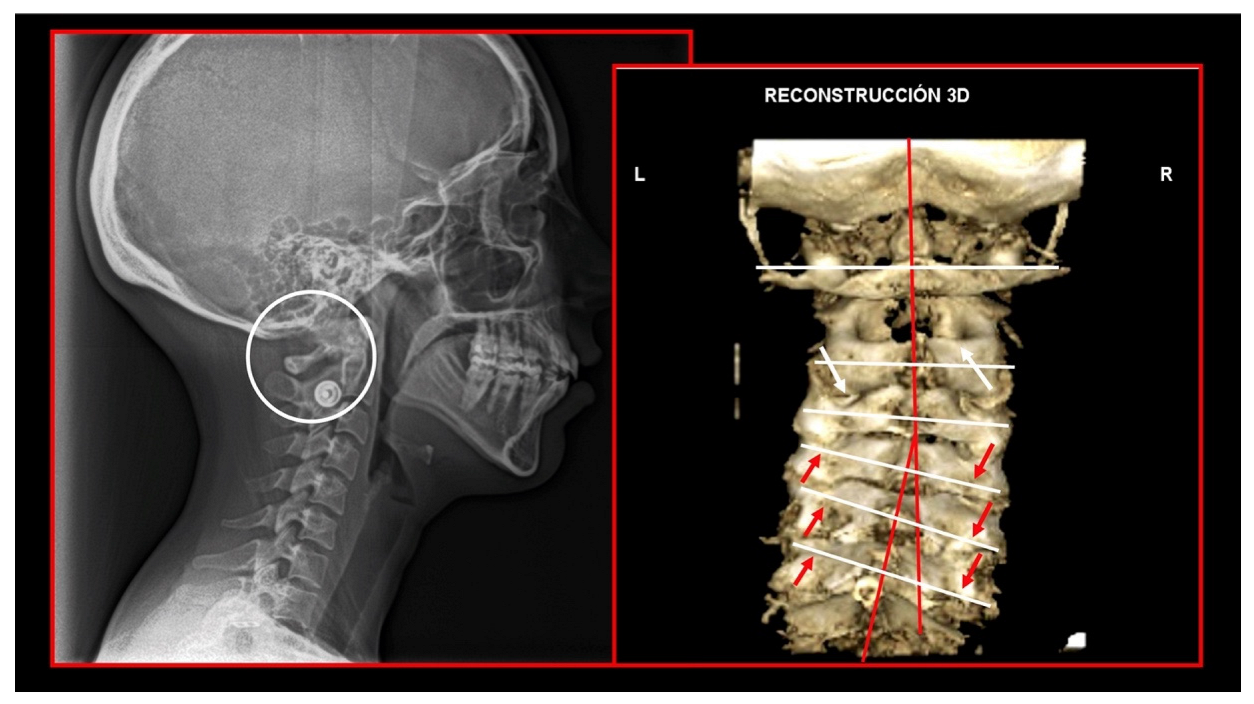

10.1. Neck X-ray

11.5. Axis and Atlas Derotation